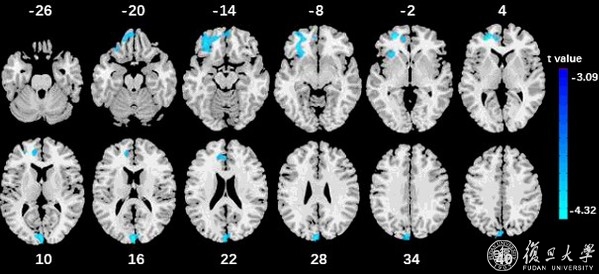

该研究利用大型的欧洲青少年群体神经科学影像学随访队列(n=1963),发现前额叶(特别是腹内侧前额叶、背侧前扣带回和前岛叶)和枕叶区(特别是左侧楔叶)的灰质体积越小,多动症的症状越严重(图1)。

图1: 前额叶和枕叶区的灰质体积越小多动症症状越严重